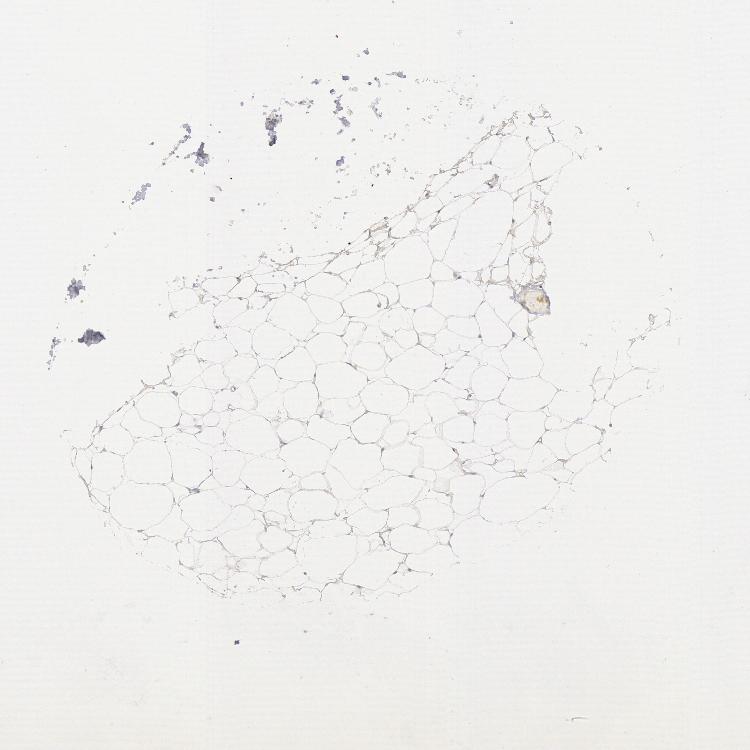

ADIPOSE TISSUE - Antibody stainingi

Antibody staining in the annotated cell types in the current human tissue is reported as not detected, low, medium, or high, based on conventional immunohistochemistry profiling in selected tissues. This score is based on the combination of the staining intensity and fraction of stained cells.

Each image is clickable and will lead to virtual microscopy that enables deeper exploration of all samples and also displays staining intensity scores, fraction scores and subcellular localization as well as patient and tissue information for each sample.

Antibody HPA001380Antibody CAB025863

Adipocytes Not detectedNot detected